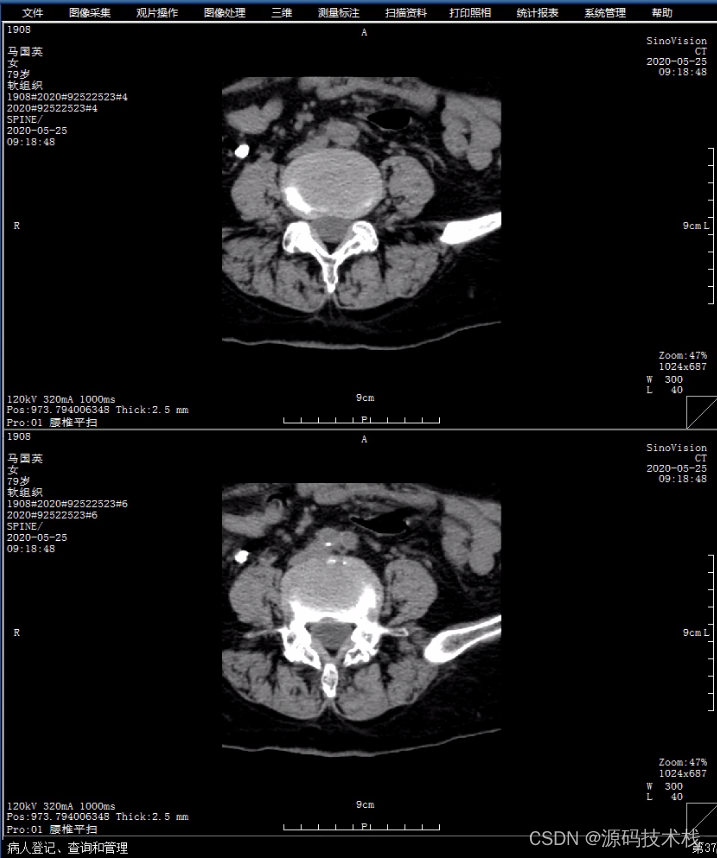

PACS是Picture Archiving and Communication Systems首字母缩写,全称为影像储存和传输系统,涉及放射医学、计算机技术、通讯技术及数字图像技术等,是医院信息系统的重要组成部分,是将数字医疗设备(如X线、CT、MRI、超声、病理等)所产生的医疗图像进行获取、储存、管理、诊断及信息处理的重要系统。PACS集医疗图像获取、数据储存、图像的显示和处理、数据管理及传输影像等技术为一体,大大降低了医生对传统硬拷贝技术的依赖。

PACS主要包括图像获取、图像传输、图像储存和管理、图像影像工作站进行阅读四个流程。临床上,PACS系统流程从患者在登记台登记检查开始,然后患者进入检查室,技师进行检查,采集影像数据,将采集的影像数据进行上传至PACS网,影像医师通过PACS调阅图像并书写报告,最后将PACS的图文报告归档。

PACS改变了传统图像保存和传递方式,成本低,保存时间长,方便图像的存取,使影像医师和临床医师能够随时读取影像资料。